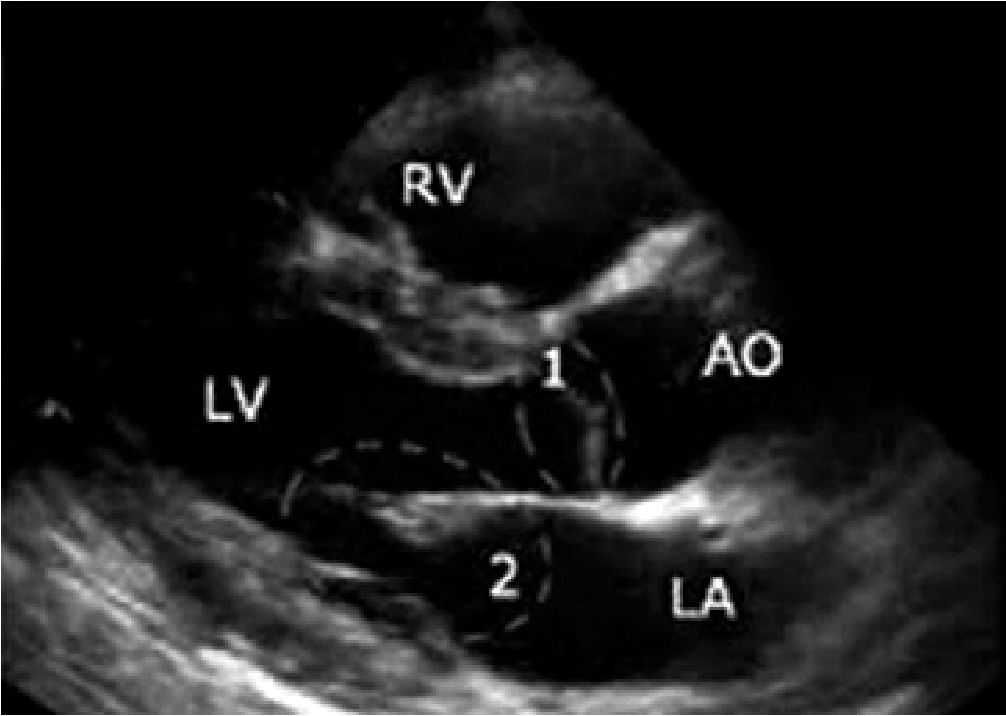

Figura 5. Eje largo paraesternal. 1: Válvula Aortica; 2: Válvula mitral. Se observa contacto del velo anterior de la válvula con el septum, signo de hipovolemia[20].

Además, en PSAX, la presencia del signo de los músculos papilares “besándose” o en PLAX (Figura 4), el contacto de velo anterior de la válvula mitral con el septum (Figura 5), apoyan la presencia de hipovolemia en contexto de sepsis, por lo cual está indicado la administración de fluidos guiado por metas. Debemos considerar que estos parámetros también dependen de la postcarga, motivo por el cual, a menor postcarga pueden presentarse incluso en ausencia de hipovolemia.